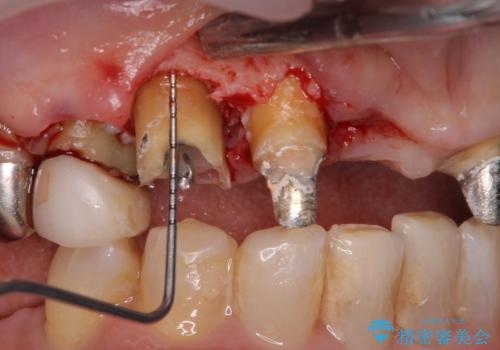

まずは土台の歯を引っぱり出し、外科処置により歯肉の状態を十分に整えた上で、オールセラミッククラウンにて補綴することとしました。

元々の土台は歯肉の中に埋もれており、歯肉が著しく腫れている状態だったため、歯を引っぱり出すこととしました。引っぱる期間は2ヶ月ほどで済み、その後歯周外科処置を行ったことで、土台周りの歯肉は腫脹のない健全な状態へと改善されました。